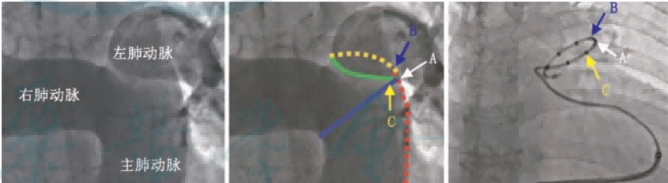

手术中,团队根据 DSA 肺动脉造影,结合术前肺动脉 CTA 影像,选择最佳型号的 PADN 消融导管,确定消融靶点后,精准消融。

团队通过科学诊断、充分评估,成功应用全球首创、中国原创的 PADN 环形肺动脉射频消融导管,对肺动脉神经节消融靶点进行「点对点」精准消融,手术顺利。PADN 术后 RHC 血流动力学参数较术前明显改善,其中,平均肺动脉压即刻下降 16%,肺毛细血管楔压即刻下降 25%。术中及术后患者无不适,生命体征平稳,安返病房,此次手术圆满成功。